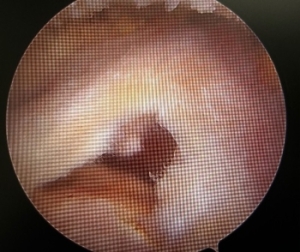

疼痛が強く挙上困難な腱板断裂に対して関節鏡下腱板縫合術(ARCR)を行っています。これにより関節切開で行う従来法と比較し低侵襲で疼痛も少なく早期機能回復が可能となりました。比較的軽微な断裂やインピンジメント症候群に対しては関節鏡下肩峰形成術(ASD)を行い早期社会復帰を目指します。

c.腱板断裂 d.鏡視下縫合後